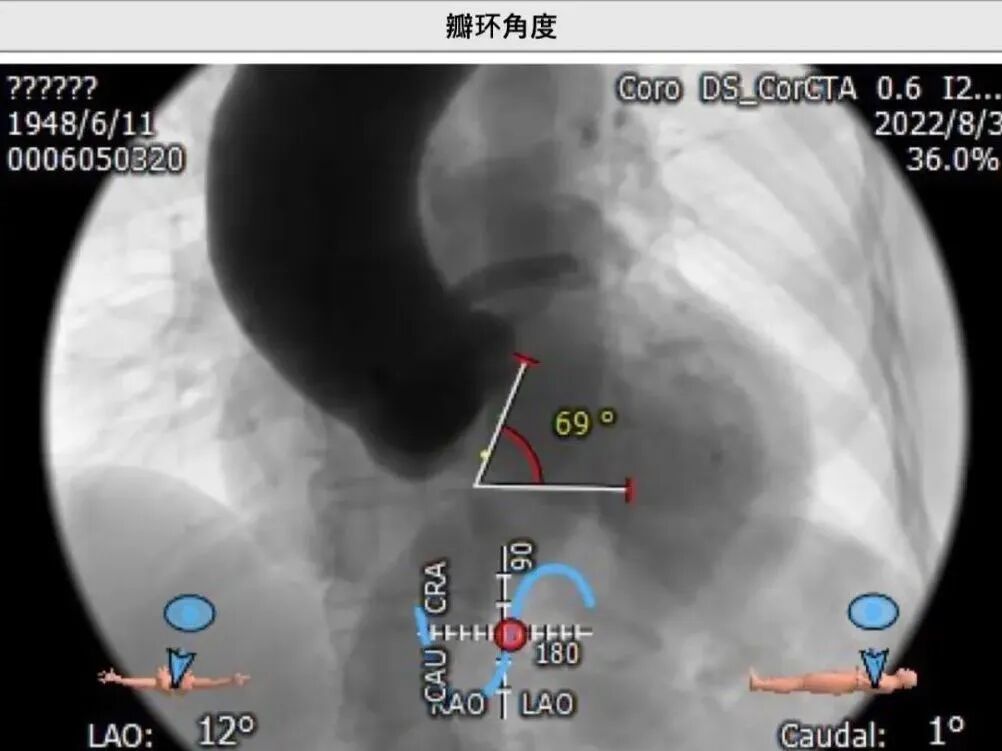

瓣环角度:69o

杨毅宁院长总结了该病例特点:

● 患者为高龄女性,主动脉瓣中度狭窄合并中重度返流;

● 患者升主动脉扩张,横位心角度较大69o,存在升主破裂风险;

● 患者瓣环及流出道无钙化,存在瓣膜移位可能。